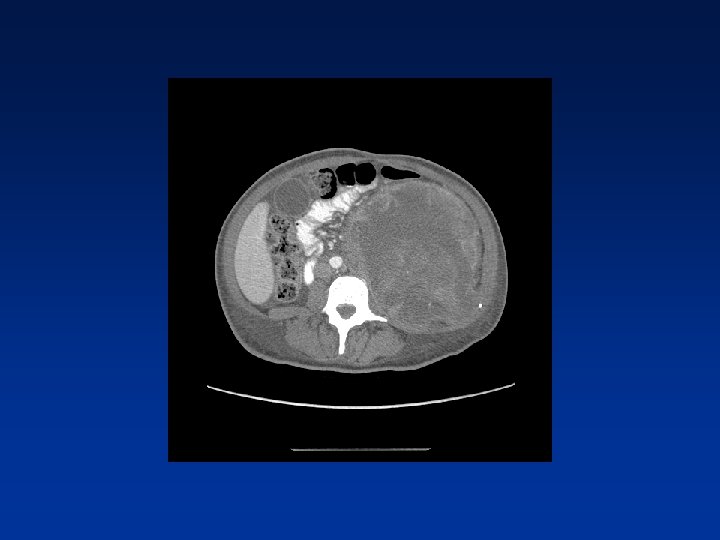

CASE